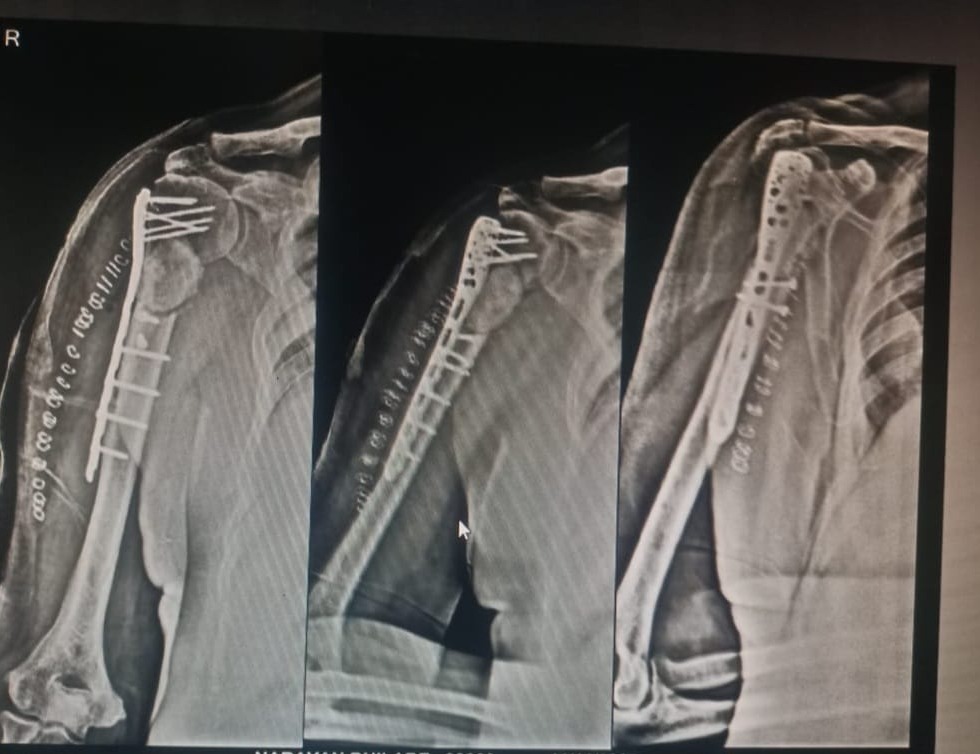

Pathological proximal humerus fracture fixation !